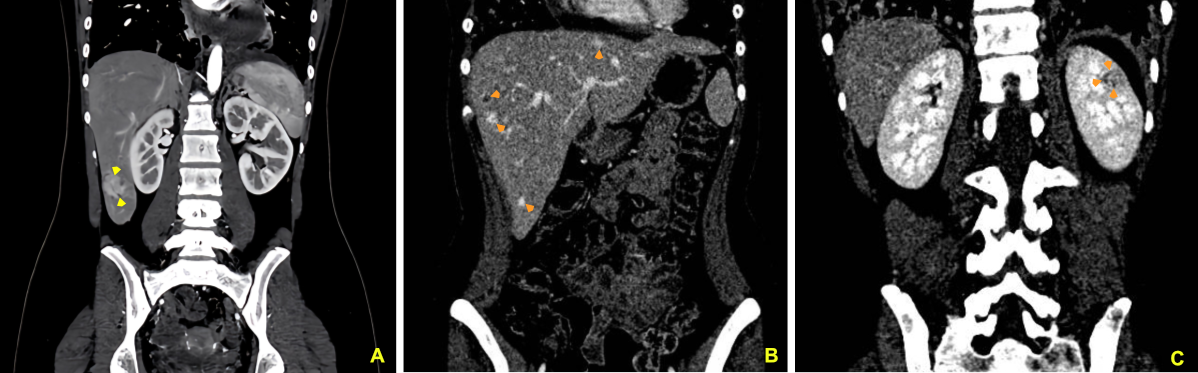

Case Presentation: A 17-year-old female presented with a one-month history of persistent dry cough, worsened by lying flat, requiring multiple pillows to sleep comfortably. Initially treated for presumed pharyngitis, her symptoms persisted, prompting further evaluation. Echocardiography revealed a large pericardial effusion with a normal ejection fraction, leading to hospital admission. Imaging studies identified a 3.5 x 4.0 cm irregular mass in the right atrium, thickened pericardial membranes, and significant pericardial effusion. Computed tomography (CT) scans also showed nodules in the mediastinum, lungs, and liver, along with a skull mass. Cardiac magnetic resonance imaging (MRI) confirmed a 5.0 x 3.0 x 4.0 cm hyperintense mass in the right atrium on T2-weighted images. Biopsy of a liver lesion confirmed angiosarcoma of cardiac origin. Despite initiating chemotherapy, the patient discontinued treatment after six months due to poor response. Follow-up imaging revealed disease progression with new lesions in the liver and left kidney.